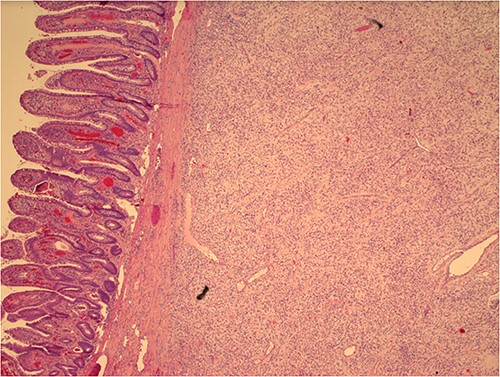

Histological examination later showed a 3.5 cm grayish color mass without aspects of cellular atypia or mitotic activity; the immunohistochemical analysis did not present aspects referable to GIST or leiomyomatosis; the overall morphological and immunophenotypic picture allowed the diagnosis of IFP (Vanek’s tumor) (Fig. 2). “All procedures performed in this study were in accordance with the ethical standards of the institutional and/or national research committee(s) and with the Helsinki Declaration (as revised in 2013).”

Histological image of Vanek’s tumor with intact intestinal mucosa.